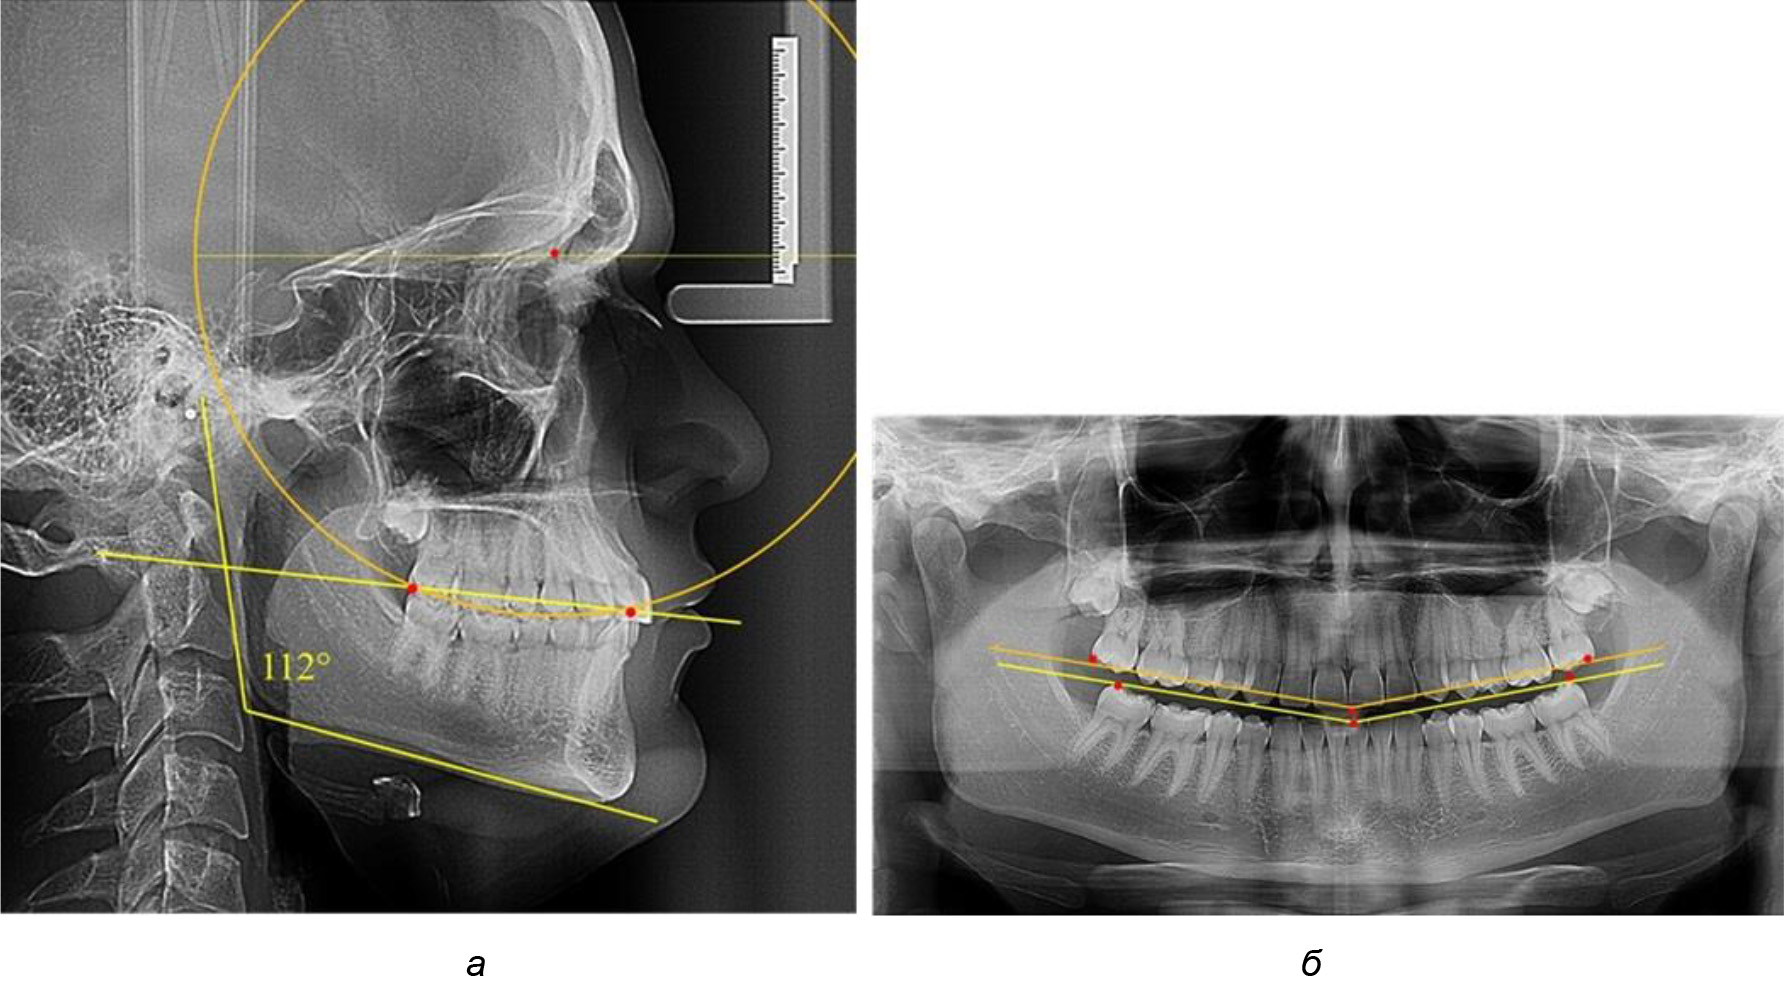

Таким образом, проведенное лечение техникой «прямой» дуги способствует нормализации окклюзионного равновесия и торку передних зубов, однако не соответствует оптимальному окклюзионному статусу, характеризующему физиологическую окклюзию. При этом величина нижнечелюстного угла оставалась на прежнем уровне (рис. 5).

Рис. 5. Особенности ТРГ при патологической кривой Spee до лечения (а) и после лечения (б) техникой «прямой» дуги

После лечения пациентов техникой «прямой» дуги, так же как и в 1-й подгруппе, было отмечено увеличение сагиттального размера окклюзионной лини в среднем на (2,38 ± 0,83) мм. Окклюзионная линия практически касалась окклюзионного контура всех жевательных зубов, и отмечалось практически полное отсутствие кривой Spee, так же как и у людей 1-й подгруппы 2-й группы (рис. 6).

Рис. 6. Особенности ТРГ при оптимальной кривой Spee до лечения (а) и после лечения (б) техникой «прямой» дуги

Таким образом, проведенное лечение техникой «прямой» дуги способствует нормализации окклюзионного равновесия и торку передних зубов, однако не соответствует оптимальному окклюзионному статусу, характеризующему физиологическую окклюзию. При этом величина нижнечелюстного угла оставалась на прежнем уровне.